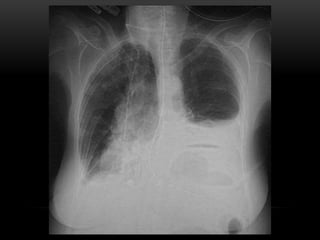

• Pathologic changes. Irrespective of the underlying mechanism

in the pathogenesis of pulmonary oedema, the fluid

accumulates more in the basal regions of lungs. The thickened

interlobular septa along with their dilated lymphatics may be

seen in chest X-ray as lines perpendicular to the pleura and are

known as Kerley' lines.

ACUTE PULMONARY OEDEMA